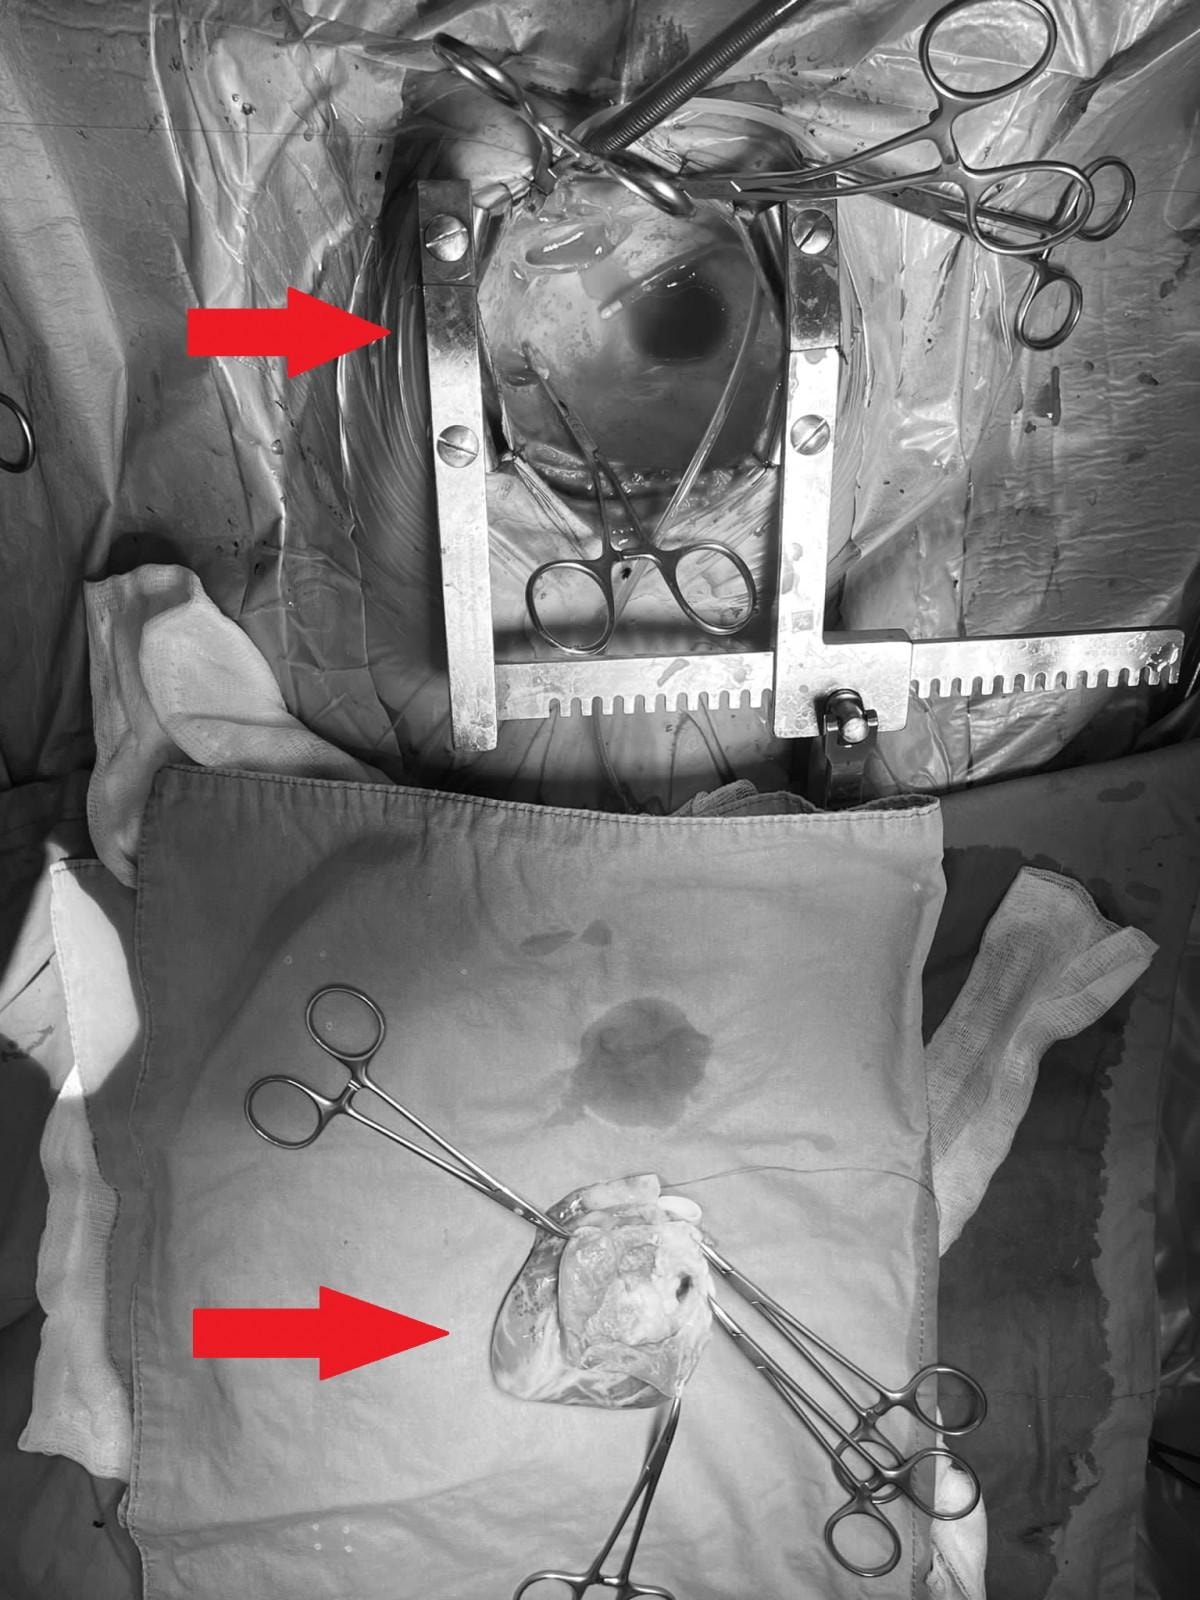

8 saat süren ameliyat sırasında Ekin Ada'nın kalbini "yerinden söküp" tümörü ameliyat masasında temizledikten sonra tekrar nakleden, “yüzyılın kalp cerrahları" arasında anılan Prof. Dr. Afksendiyos Kalangos ve Opr. Dr. Yılmaz Zorman, bu eşi benzeri olmayan operasyonu,

Tümörün içinden hayati bir damarın geçmesi nedeniyle kalp yerindeyken ameliyat etmenin imkansız olduğunu anlatan Prof. Dr. Kalangos, çok büyük bir riske girerek kalbi yerinden çıkarıp, ameliyat etme yolunu seçtiklerini vurguladı. Prof. Dr. Kalangos,

Çok dikkatli çalışmamız gerekiyordu o nedenle kalbi yerinden söktük, damarlarından ayırdık ve masanın üzerine yatırarak (kalp vücuttan ayrıyken) ameliyata devam ettik. Göğüs boşluğu tamamıyla boş kaldı, 'kalpsiz' bir durumda makineye bağlı takip edildi. Kalbi masanın üzerinde sol karıncığa hasar vermeden, hem kasları hem arterleri koruyarak açtık. Dr. Yılmaz Zorman ile beraber nefesimizi tuttuk, ince ince, soğan kabuğu soyar gibi kalp kasından tümörü ayırdık. Tümörün içinden geçen o ince, bir milimetrelik koroner damarı bulduk ve onu da titiz bir şekilde tümörden ayırarak kalbi tamamen temizledik. Onarılmış kalbi tekrar yerine taktık.